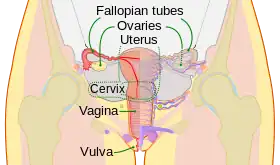

A pictorial illustration of the female reproductive system | |

9. Vagina: 10. Hymen; 11. Lumen; 12. Wall; 13. Fornix (lateral)

14. Uterus: Parts: 15. Cervix; 16. Body and 17. Fundus. 18. Orifices: External and Internal; 19. Cervical canal; 20. Uterine cavity; Layers: 21. Endometrium; 22. Myometrium and 23. Perimetrium

24. Fallopian tube: 25. Isthmus; 26. Ampulla; 27. Infundibulum; 28. Fimbria (with 29. Fimbria ovarica)

30. Ovary

31. Visceral pelvic peritoneum: 32. Broad ligament (with 33. Mesosalpinx; 34. Mesovarium and 35. Mesometrium)

Ligaments: 36. Round; 37. Ovarian; 38. Suspensory of ovary

Blood vessels: 39. Ovarian artery and vein; 40. Uterine artery and veins; 41. Vaginal artery and veins

Other: 42. Ureter; 43. Pelvic floor (Levator ani); 44. Femoral head; 45. Hip bone; 46. Internal iliac vessels (anterior branches); 47. External iliac vessels; 48. Abdominal cavity